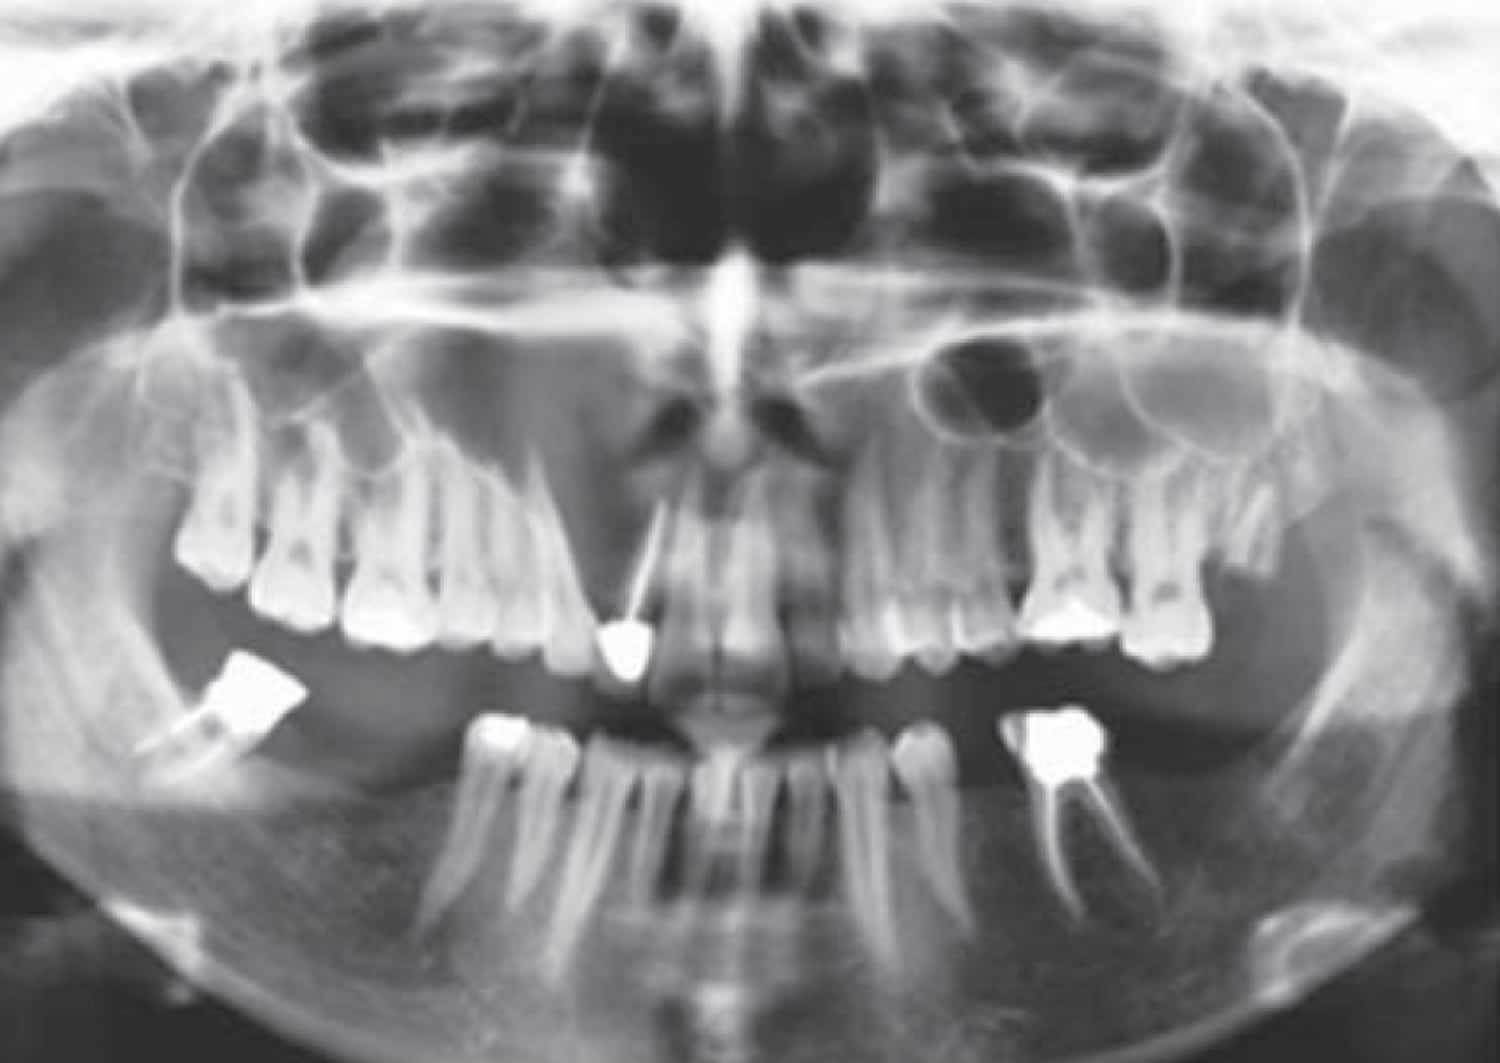

Treatment planning was explained to him and he consented to surgery. Odontogenic keratocysts make up around 19 of jaw cysts. Treatment of the odontogenic keratocyst involves meticulous resection to completely remove the lesion followed by reconstruction of the jaw with bone grafting.

Enucleation of the cyst and removal of the associated teeth. It was first described by H P Philipsen in 1956 as an odontogenic keratocyst. Download Citation Removal of Odontogenic Keratocyst in Maxilla Through the Le Fort I Osteotomy The odontogenic keratocyst is a lesion with specific clinical and histopathological aspects.

The excision of the overlying mucosa. Odontogenic keratocyst is one of the most aggressive odontogenic cysts with a high recurrence rate this was explained histopathologically as it typically shows a thin friable wall which is often difficult to enucleate from the bone in one piece and have small satellite cysts within the fibrous wall. Immediate mandibular reconstruction with a corticocancellous iliac crest bone graft.

It most often affects the posterior mandible and most commonly presents in the third decade of life. Osteotomy in the trigonoretromolar region until the exposure of the lesion. Enucleation of the lesion.

Removal of the cyst with removal of surrounding bone and or cryosurgery intense cold is applied to the cyst and bone are the most common forms of treatment. Regardless of the size of the lesion or treatment modality continued clinical. First described by Philipsen in 1956 the odontogenic keratocyst is characterized by a large squamous keratinization of its border an aggressive growth and a.

Jaw Reconstruction Surgery With Bone Graft Odontogenic Keratocyst